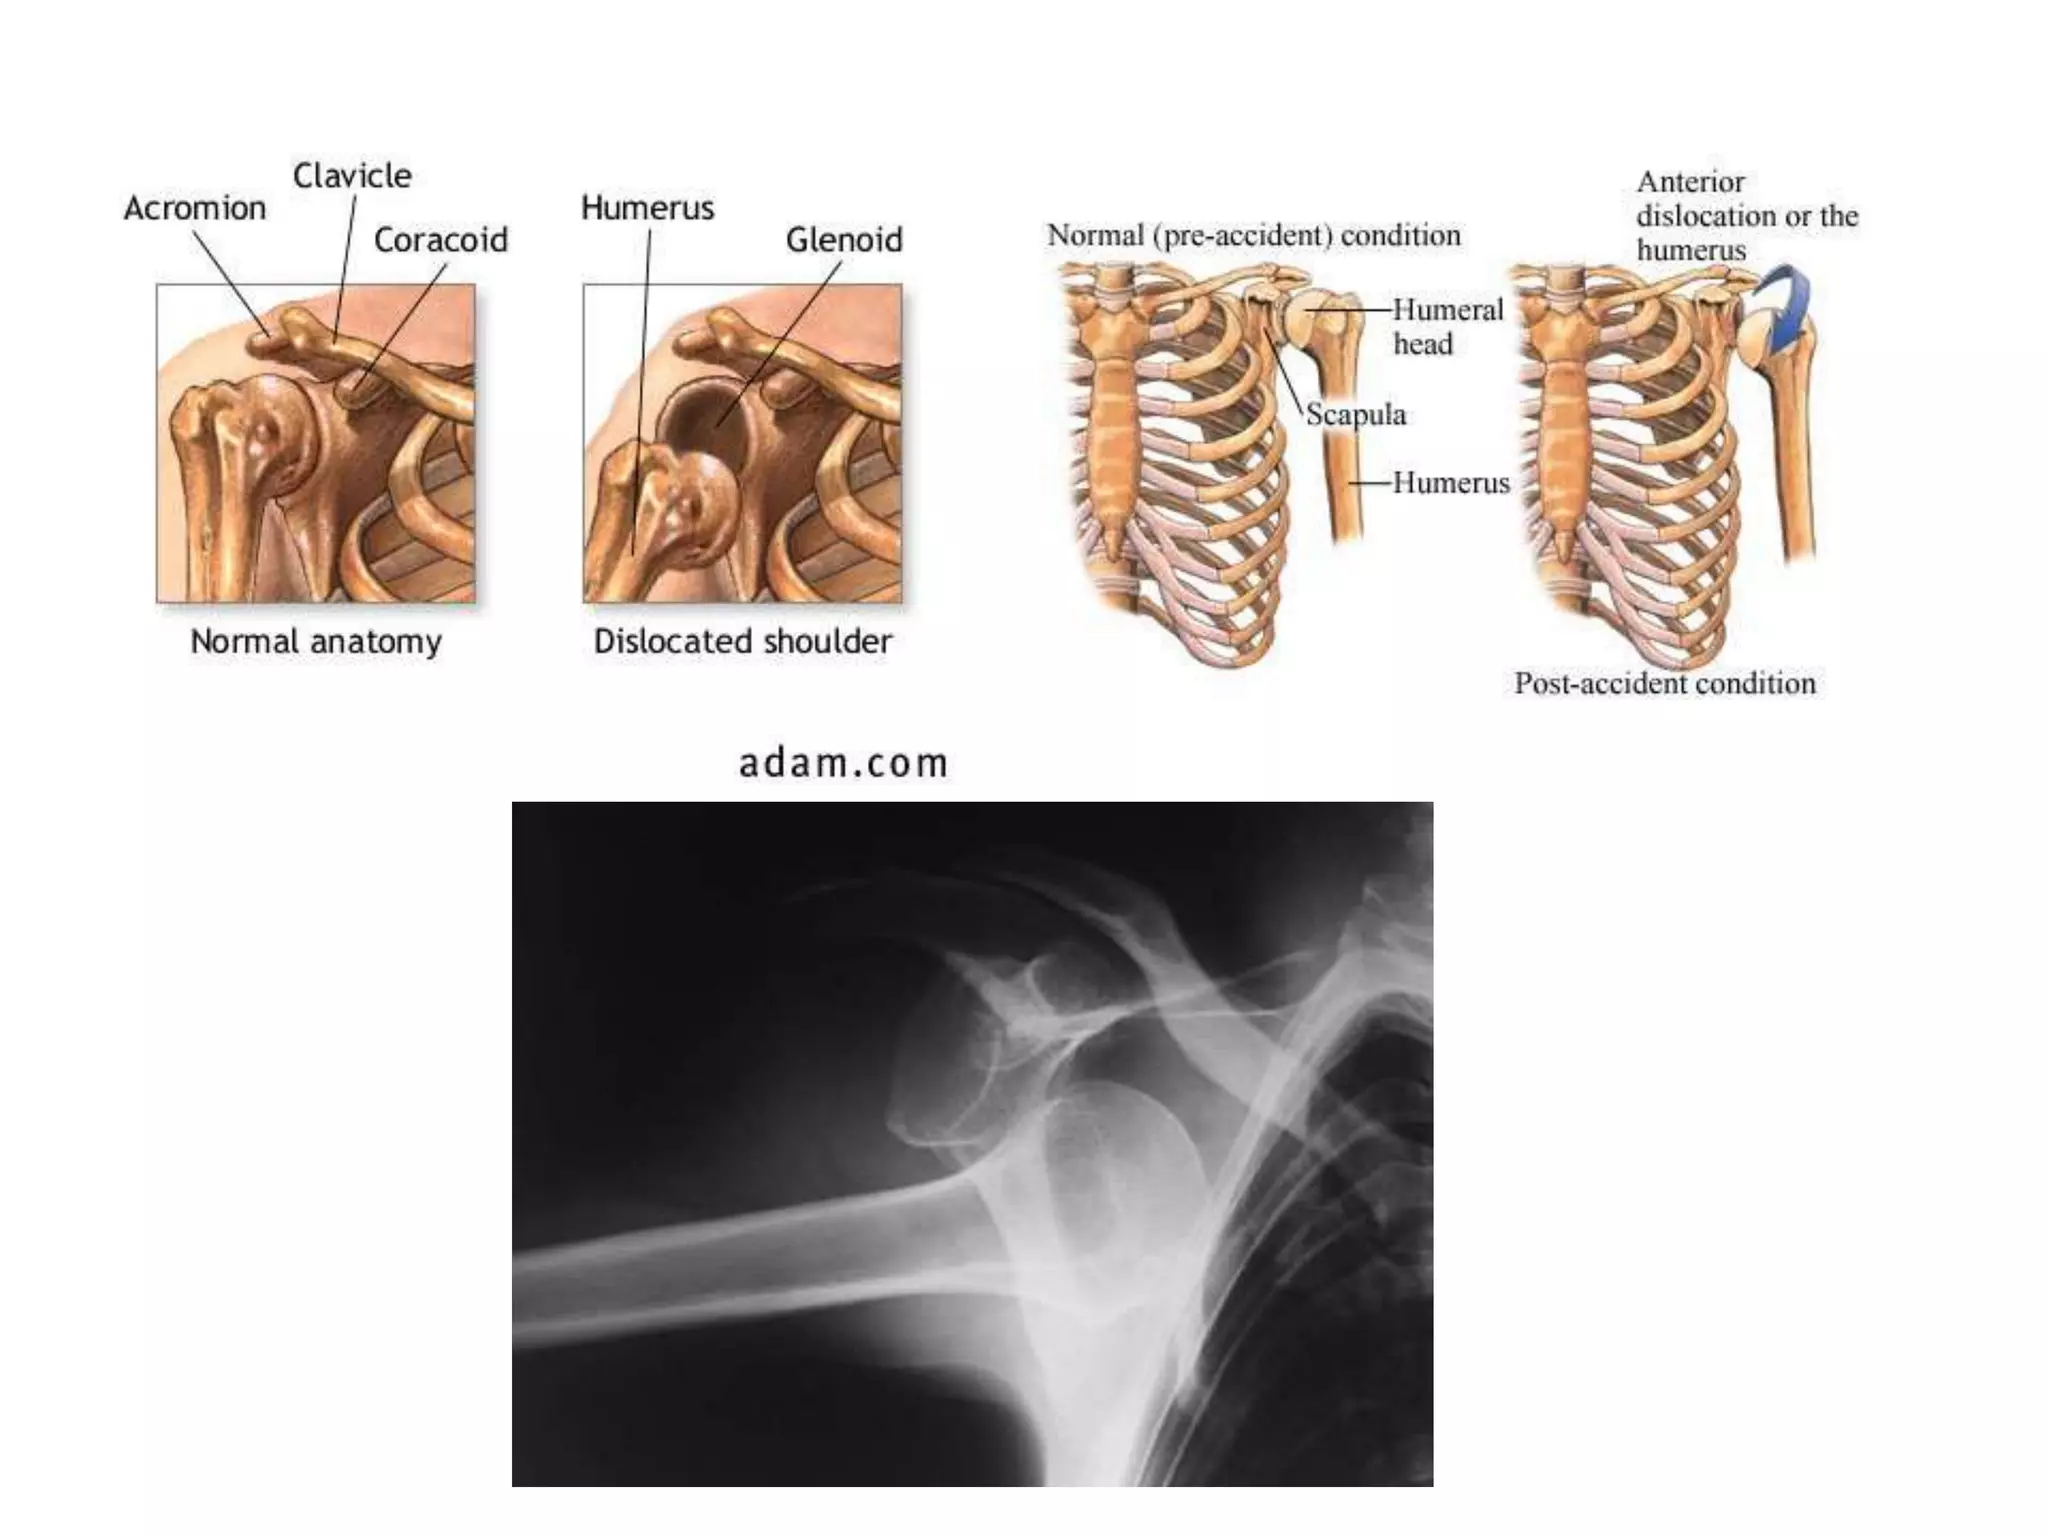

• INTRA ARTICULAR FRACTURE

Intra articular fracture